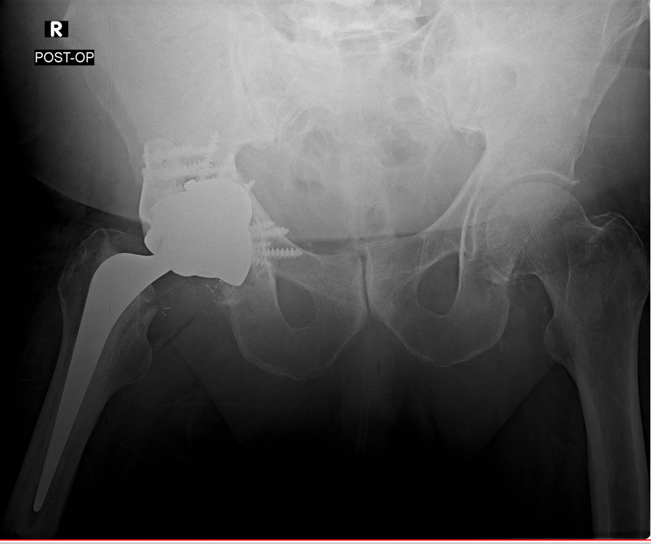

Case: 74 yo M w/ hx metastatic prostate cancer right acetabulum s/p radiation therapy with increasing right hip pain with known pathological acetabular fx. Surgical plan? Would you change implants or plan given hx of radiation therapy?

Anterior column fracture that extended into superolateral rim. Large (40% surf area) superior defect from prev irradiated bone. Cup cage reconstruction with half cage technique w/ augment in sup defect, cemented dual mobility liner, cemented femoral stem.